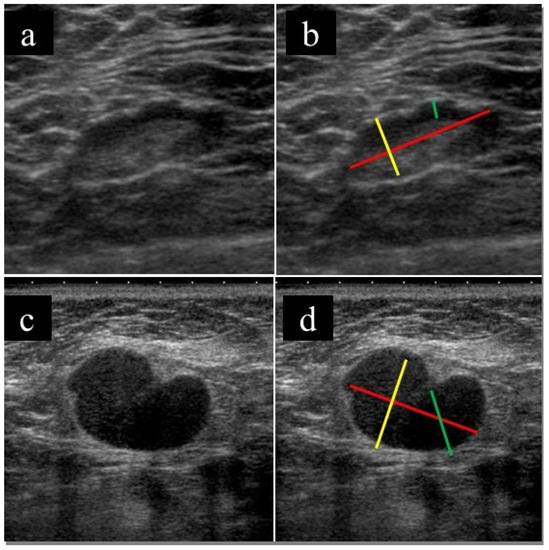

US imaging findings of the lymph nodes were retrospectively evaluated by a breast radiologist (with 11 years of experience); the evaluator was blinded to all clinical information other than the presence of lymphadenopathy. Lymph node short and long diameters, cortical thickness, and absence of fatty hilum were evaluated. Figure 1 shows a representative example of the assessment method. In the case of multiple lymph node involvement, the radiologist evaluated the lymph nodes that were biopsied.

Figure 1. Example of the assessment method for lymph nodes. (a,c) Original US images and (b,d) US images after assessment of lymphonodes. The red line shows the major axis diameter, the yellow line shows the minor axis diameter, and the green line shows the thickness of the cortex (b,d). Fatty hilum is present (a), and fatty hilum is absent (c).